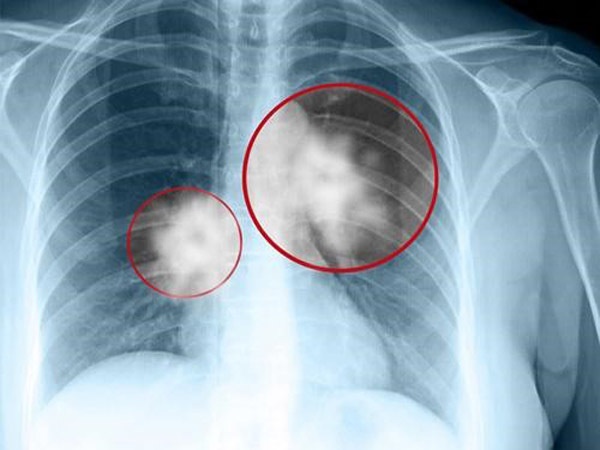

Từ hình ảnh X-quang, bác sĩ nói phổi của cô có màu trắng lớn, đó là viêm bạch huyết ung thư, có nghĩa là ung thư phổi di căn. Thật đáng tiếc khi không còn thời gian để phẫu thuật và hóa trị. Chỉ trong 5 ngày, hơi thở của Tiểu Mơ ngày càng yếu đi và qua đời